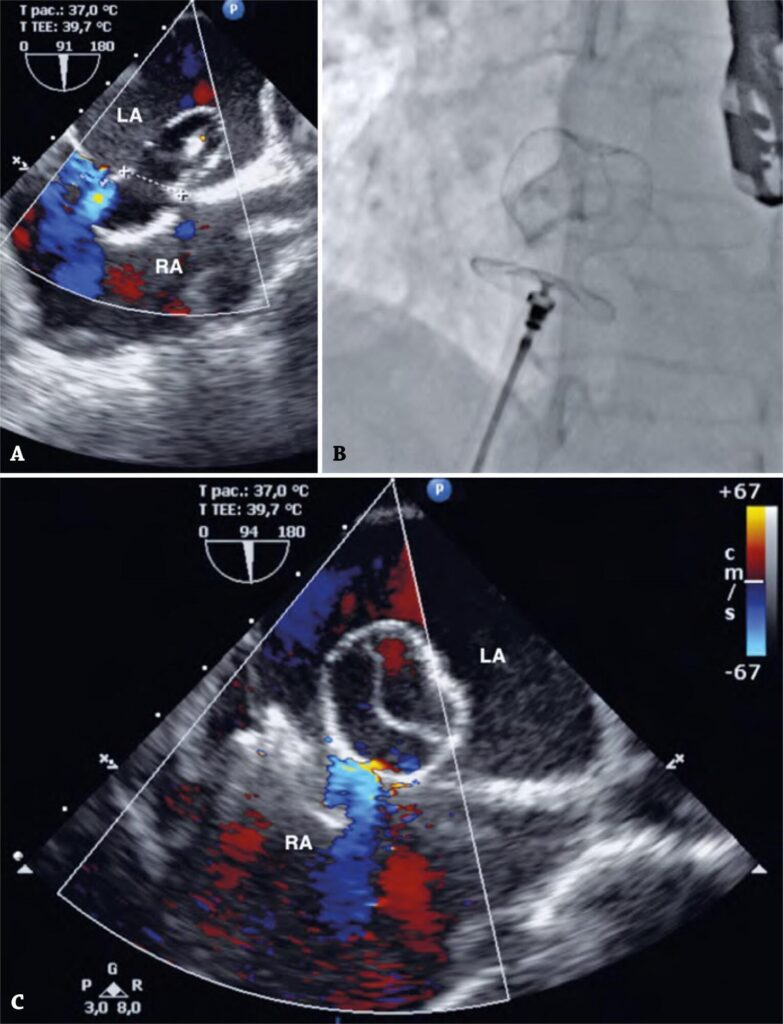

Paciente do sexo feminino, 47 anos, foi encaminhada para fechamento transcateter de comunicação interatrial (CIA) do tipo ostium secundum. O acesso vascular foi realizado pela veia femoral direita, e o diâmetro da CIA (16mm) foi medido com uso de balão e técnica de parada de fluxo (stop-flow) ().

Figura 1

(A) Imagem de ecocardiografia transesofágica mostra diâmetro da comunicação interatrial de 16mm, medida com balão e técnica de parada de fluxo (stop-flow). (B) O dispositivo CeraFlex™ ASD Occluder de 16mm mostra o formato de tulipa do disco atrial esquerdo, após remoção do cateter de entrega de 12F. Imagens de fluoroscopia em duas incidências. (C) Imagem de ecocardiografia transesofágica.